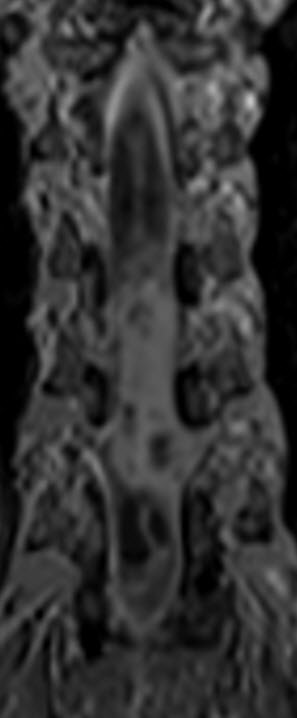

MRI of the dorsal spine with contrast and myelography and fibertraking and spectroscopy showing the recent lesions as seen in the below pictures with abscess formation.

MRI showing the new flare with abscess malformation and the old one

Spectroscopy confirming the tbc abscess nature of the flare. High lipid and the choline is due to contamination of the voxel.